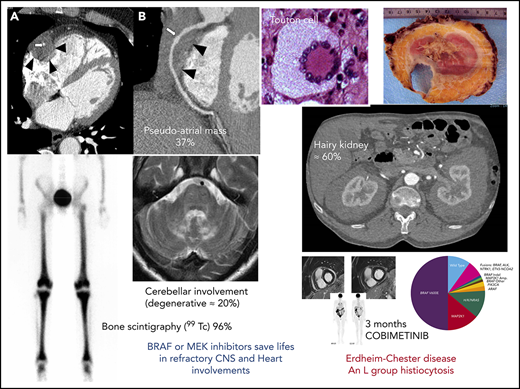

Erdheim-Chester disease (ECD) is characterized by the infiltration of tissues by foamy CD68+CD1a− histiocytes, with 1500 known cases since 1930. Mutations activating the MAPK pathway are found in more than 80% of patients with ECD, mainly the BRAFV600E activating mutation in 57% to 70% of cases, followed by MAP2K1 in close to 20%. The discovery of BRAF mutations and of other MAP kinase pathway alterations, as well as the co-occurrence of ECD with LCH in 15% of patients with ECD, led to the 2016 revision of the classification of histiocytoses in which LCH and ECD belong to the “L” group. Both conditions are considered inflammatory myeloid neoplasms. Ten percent of ECD cases are associated with myeloproliferative neoplasms and/or myelodysplastic syndromes. Some of the most striking signs of ECD are the long bone involvement (80%-95%), as well as the hairy kidney appearance on computed tomography scan (63%), the coated aorta (40%), and the right atrium pseudo-tumoral infiltration (36%). Central nervous system involvement is a strong prognostic factor and independent predictor of death. Interferon-α seems to be the best initial treatment of ECD. Since 2012, more than 200 patients worldwide with multisystem or refractory ECD have benefitted from highly effective therapy with BRAF and MEK inhibitors. Targeted therapies have an overall, robust, and reproducible efficacy in ECD, with no acquired resistance to date, but their use may be best reserved for the most severe manifestations of the disease, as they may be associated with serious adverse effects and as-yet-unknown long-term consequences.

The most frequent manifestation of ECD is long-bone osteosclerosis (Figure 1), which is observed in 80% to 95% of patients,11,12 and is symptomatic in 38%. It may cause mild leg bone pain,12 sometimes requiring nonsteroidal anti-inflammatory drugs or opioid treatment. Long-bone involvement is a hallmark of the disease.13 It may be detected by radiological imaging (X rays in the past, computed tomography [CT] scans and magnetic resonance imaging [MRI] more recently), or bone scintigraphy (99Technetium [99Tc]), revealing increases in radiotracer uptake by the distal ends of the femurs and the proximal and distal tibia. The latter have now largely been replaced by positron emission tomography-CT (PET-CT) showing avid FDG uptake in the legs detected in about 95% of patients. 18FDG-PET scans are particularly informative for assessments of ECD activity, in particular for therapeutic responses.19

Typical clinical and imaging features of ECD. (A) Mass of the right atrium and of the atrioventricular sulcus (blue arrows). (B) Hypermetabolism of long bones, aorta, and right atrium in 18 fluorodeoxyglucose PET. (C) Pseudotumoral infiltration of brain (MRI, T1 weighted image with gadolinium), yellow arrow. (D) Typical xanthelasma palpebrarum

Progress in radiological imaging has greatly facilitated the detection of cardiovascular involvement. CT scan may reveal the sheathing of whole aorta (“coated aorta”), a classic feature of ECD (40% of our 261 cases). Peri-aortic infiltration may also affect either the thoracic or the abdominal portion of the aorta, and may extend to the main branches of the aorta.11,12,20 It is usually asymptomatic, and is not associated with dilation, dissection, or aneurysm. The infiltration of coronary arteries is seen in 23% of patients,11 and can be complicated by coronary stenosis and myocardial infarction.20 Pericardial disease is frequent (29%). It may present as pericarditis, pericardial effusion, or cardiac tamponade, and may be fatal.20

Right atrium (RA) pseudotumor, another classical feature of ECD, can be observed by dedicated MRI in 36% of patients.11,12,20 Dedicated cardiac MRI is the most appropriate type of imaging for assessments of cardiac manifestations of ECD, whereas aortic CT scans should be preferred for evaluations of peri-aortic sheathing.21 A recent retrospective study of cardiac imaging in 205 patients with ECD reported abnormal results for 101 patients (49%), including 72 with an impaired right ventricular atrioventricular sulcus (72%) and 65 with an impaired RA enclosure (64%).22

Retroperitoneal fibrosis is observed in a third of patients with ECD, sometimes complicated by bilateral hydronephrosis (27%), potentially requiring ureteral stenting.23 Pelvic ureter involvement has never been described, and the inferior vena cava is rarely affected. In ECD, fibrosis entirely encircles the aorta; in contrast, the posterior wall of the aorta is rarely affected in idiopathic retroperitoneal fibrosis.20 It should be noted that sheathing is observed not only around the aorta and the renal capsule but also often around the proximal portion of the ureters, and this is the cause of ureteral obstruction in most patients. In rare cases, the renal/perirenal lesions may be misdiagnosed as xanthogranulomatous pyelonephritis, with patients even undergoing bilateral nephrectomy in some cases.24 Abdominal CT scans reveal fat infiltration around the kidneys (“hairy kidneys”) in 63% of patients.11,12

Nervous system, facial, and orbital manifestations

As in LCH, neurological involvement in ECD may have a tumoral or degenerative presentation. Many different central nervous system (CNS) manifestations are observed in ECD. The most frequent neurological signs are cerebellar and pyramidal syndromes (41% and 45% of cases, respectively), but seizures, headaches, sensory disturbances, neuropsychiatric signs, cognitive impairment, cranial nerve palsy, and asymptomatic lesions have also been reported.29 Degenerative involvement of the cerebellum is observed in 17% of patients and is very difficult to treat. On MRI, CNS manifestations may appear as enhancing masses or high signal density. Imaging shows diffuse thickening or dural masses indicative of meningeal involvement in 23% of patients.30 CNS involvement can lead to severe disability, and survival analysis has identified this factor as an independent predictor of death (hazard ratio, 2.51).31 Intracranial vascular infiltration, particularly in the basilar artery vessels, is also observed in some patients with ECD and can lead to ischemic stroke. Five patients of our current series have an important infiltration around intracranial arteries, especially the basilar trunk. This peri-arterial intracranial encasement is far less frequent than the coated aorta. CSF findings are usually normal in neurological ECD.